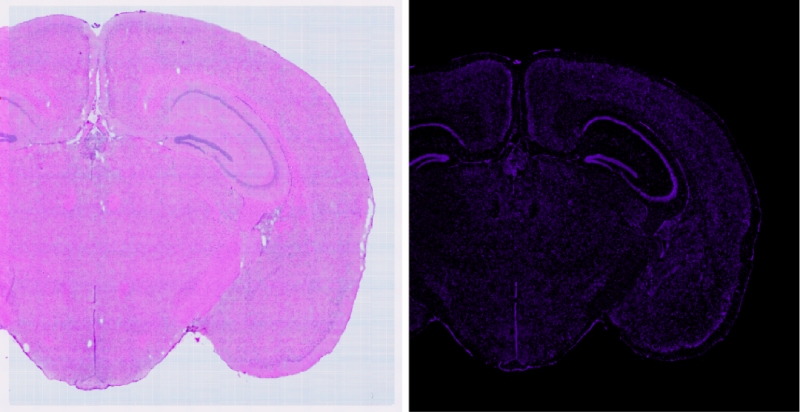

在生命科學的探索之旅中,技術的每一次革新都是我們深入理解生命奧秘的堅實基石。百邁客生物推出顯微掃描儀領域的旗艦力作——BH1000掃描儀,它將引領我們邁入空間組學成像的新紀元。BH1000掃描儀不僅可以實現(xiàn)人體、動物、植物以及各類玻片標本的快速全切片掃描成像,更以其卓越的性能全面滿足百創(chuàng)空間組學實驗的高端成像需求。其可以實現(xiàn)明場以及熒光的原片高清無錯成像,結合百創(chuàng)S空間系列細胞分割算法,能夠實現(xiàn)精準的空間單細胞分割,為空間組學細胞層面的研究提供了強有力的支持。

在樣本完成質檢并合格后,需要對研究的目標區(qū)域進行確認,可以利用BH1000進行高清(標配高品質平場復消色差物鏡,20×物鏡,數(shù)值孔徑N.A.≥0.8,?同時最多支持拓展4個物鏡)的明場成像來進行判斷。

通過BH1000快速(20X,8mm*8mm,小于50S)得到高清明場圖像與高清的熒光(支持7個熒光通道,各通道有獨立傳感器,電動切換,標配明場、?DAPI、FITC和CY3)成像結果來選擇最優(yōu)的透化時間(需要選擇熒光最亮且符合相應明場結構無明顯逸散的梯度)

可以利用BH1000對明場及熒光掃描過程中經常出現(xiàn)的拼接錯誤進行校準(自主研發(fā)BMCHiper軟件,搭配自研半透半返模塊,實現(xiàn)圖像無錯校準),得到原片無錯高清的熒光圖像與原片無錯高清的明場圖像,為后續(xù)空間數(shù)據(jù)準確的定位和可視化提供基礎,使得復雜的轉錄組數(shù)據(jù)能夠轉化為最直觀,最精準的生物學見解。

BMKMANU BH1000是專門適配精準空間組學BMKMANU S系列產品的成像系統(tǒng),它不僅可以實現(xiàn)各類物種及各類玻片標本的快速全切片掃描成像,還能能夠滿足百創(chuàng)空間組學中各個實驗環(huán)節(jié)的成像需求,更能搭配使用百創(chuàng)細胞分割算法,結合其輸出的原片無錯高清明場成像,原片無錯高清熒光成像實現(xiàn)精準空間單細胞分割。